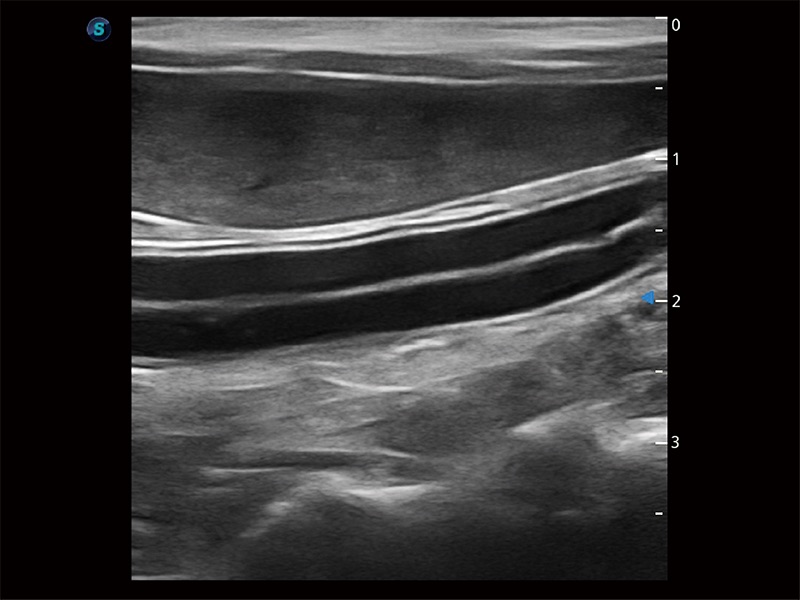

高性能和先進(jìn)的臨床應(yīng)用工具可以為動物醫(yī)生提供臨床信心。ProPet 80 搭載了先進(jìn)的腹部和淺表應(yīng)用工具,幫助醫(yī)生在日常臨床實(shí)踐中發(fā)揮前所未有的作用。

為精細(xì)結(jié)構(gòu)及組織邊緣提供高清晰度的圖像和更大的成像視野。幫助減輕醫(yī)生的用眼疲勞,快速精準(zhǔn)獲得測量的數(shù)據(jù)。